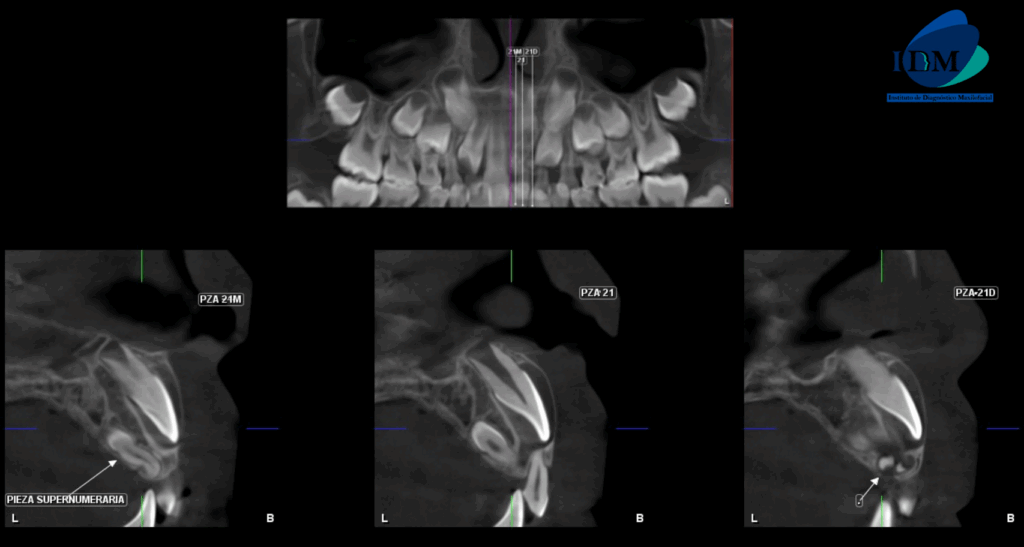

A la evaluación de la tomografía volumétrica (CBCT) en los cortes axiales (Figura 2) y transaxiales (Figura 3), se aprecia pieza supernumeraria en posición invertida localizada hacia palatino de pieza 21, segmento coronario mesial en contacto con la cortical de conducto nasopalatino. Asimismo, se observa imágenes hiperdensas circunscrita por un halo hipodenso localizado adyacente a cima del reborde alveolar a nivel de pieza 21, que ocasiona desplazamiento de pieza 21 hacia vestibular.

CORTES TRANSAXIALES